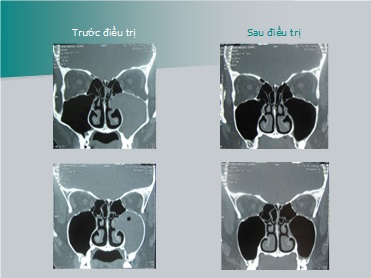

Phim X quang cắt lớp chụp hệ thống xoang trước và sau điều trị:

Bn TXD - nam, sinh năm 1980

Trước điều trị

Sau điều trị

Kết quả hồi phục hoàn toàn sau điều trị